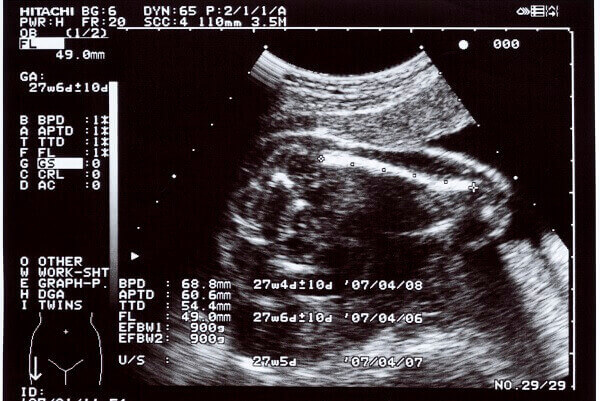

妊娠後期に内診や超音波検査に臍帯下垂がわかった場合、帝王切開になることが多いようです。